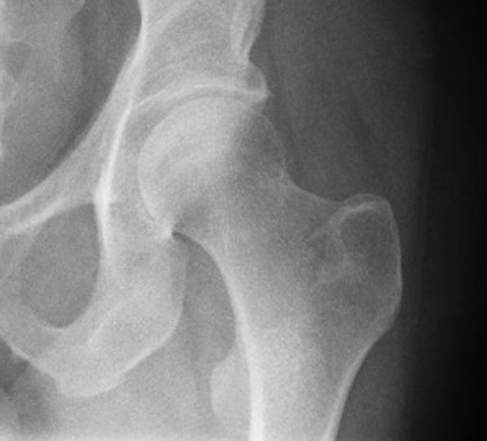

Запитання 23

НЕОПЕРОВАНИЙ ПЕРЕЛОМ ЦІЄЇ КІСТКИ І В ЦЬОМУ МІСЦІ ПРИЗВЕДЕ ДО СМЕРТІ В СЕРЕДНЬОМУ ЧЕРЕЗ КІЛЬКА РОКІВ. А ЦІ РОКИ ПЕРЕТВОРЯТЬСЯ НА СИДЯЧІ АБО ЛЕЖАЧІ МУКИ. ЯКОЇ КІСТКИ І ЯКОЇ ЇЇ ЧАСТИНИ?

варіанти відповідей

HUMERUS, ХІРУРГІЧНА ШИЙКА

ВЕРХНЬОГО ДІАФІЗА

FEMUR, ШИЙКА

ULNA, ШИЙКА

ПРОКСИМАЛЬНОГО ЕПІФІЗА

ДИСТАЛЬНОГО ЕПІФІЗА

HUMERUS, ШИЙКА

RADIUS, ШИЙКА